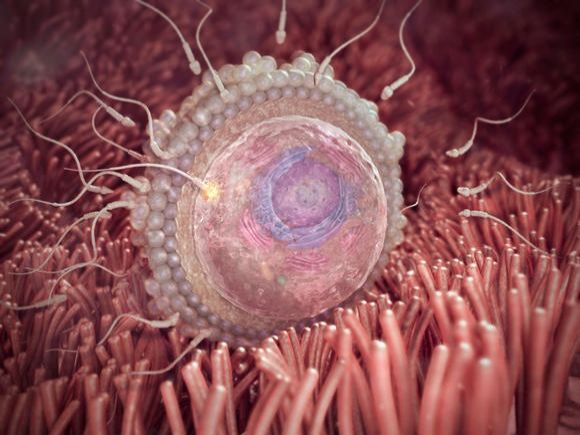

2. týden těhotenství

Maminka

V druhém týdnu těhotenství, ještě před tím, než se začne vyvíjet plod, vaše miminko, se musí připravit tělo. Od přírody je...